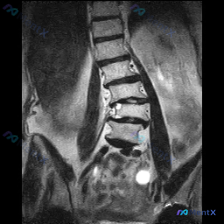

这份腰椎MRI冠状位片,第一眼除了侧弯还能发现什么关键退变征象?

目前可见的核心形态学改变比较直观,但也有细节值得留意:

- 脊柱序列明显不对,有侧弯和旋转

- 多个椎间盘的信号看着不太好

- 部分区域的空间好像有狭窄